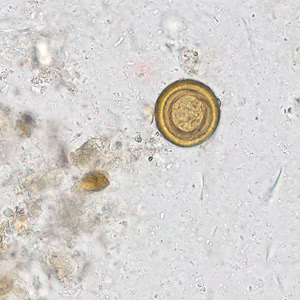

Case #281 – August, 2010

A twenty-year-old male from India presented with recurrent abdominal pain. He underwent an appendectomy at a local medical center. Sections of the appendix were obtained, sectioned, and stained with hematoxylin and eosin (H&E). Figures A–D show what was observed microscopically. What is your diagnosis? Based on what criteria?

Figure A